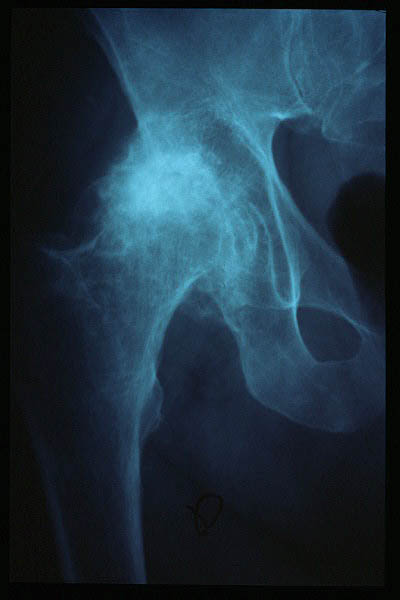

Artrosis avanzada de cadera. Anquilosis.

Artrosis anquilosante de cadera.

Atrosis avanzada de cadera.